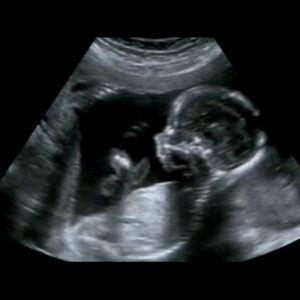

Pränatale kindernephrologische Beratung

Wird während der Ultraschalluntersuchungen in der Schwangerschaft eine Fehlbildung der Nieren, der ableitenden Harnwege oder eine andere Nierenerkrankung festgestellt, sind werdende Eltern oft verunsichert und besorgt. In solchen Situationen ist die fachliche Einordnung der Befunde durch eine eine Kinder-Nephrolog*in besonders wertvoll. Sie/er erklärt die Ergebnisse verständlich, bespricht mögliche Behandlungsschritte und unterstützt Eltern einfühlsam dabei, die Situation einzuordnen und die nächsten Schritte für die bestmögliche Betreuung ihres Kindes zu planen.